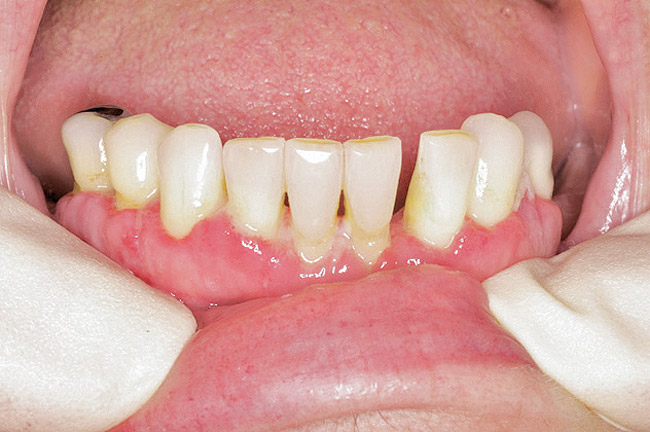

Under the sextant approach, one quadrant is treated and the patient is left to heal for 2 months before proceeding to any additional quadrants. While the patient heals, a 10-day course of antibiotics and 2 months of twice-daily chlorhexidine rinsing may be prescribed. Figure 4 shows a patient who was taking oral bisphosphonates for 3 years and was treated with the sextant approach. As seen in the radiograph, the patient has one molar in the lower right quadrant. This tooth was extracted and the patient was given 2 months to heal (Figure 5 and Figure 6). The patient was placed on antibiotics and chlorhexidine rinse. After 2 months, no signs of BRONJ were observed, and the anterior teeth were scheduled for extraction. They were extracted as atraumatically as possible, and the site was sutured (Figure 7 and Figure 8).The patient then was given another 2 months to heal, following the previous protocol. After 2 months of healing, no BRONJ was observed (Figure 9).

Then, patient was able to move forward with the prosthesis. Figure 10 shows a periodontal patient who was taking oral bisphosphonates for osteoporosis. The patient had full-mouth scaling and root planing, then was given 2 months to heal and instructed to rinse with chlorhexidine twice daily. After no signs of BRONJ were observed, the patient had full-mouth osseous surgery on her few remaining teeth in the mandible. The surgery was performed all at once and not according to the sextant approach because the patient was on a heart and lung transplant list and was moved up the list while healing from the scaling and root planing. The patient also had extensive bone loss in her anterior mandible (Figure 11).To avoid performing extractions, a simple composite splint was placed between the partial dentures (Figure 12 and Figure 13). The splint reduced the mobility of the teeth and made them less likely to be knocked out during any surgical intubation procedure.

Figure 12  Facial view of composite splint.

Figure 12